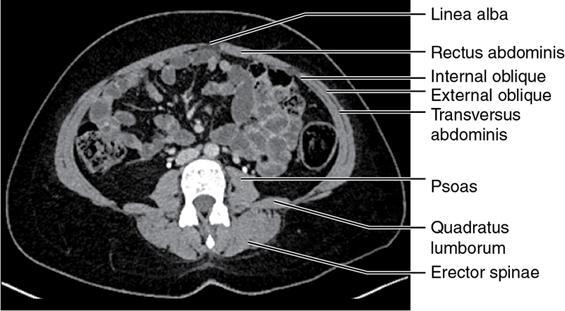

CROSS SECTIONAL ANATOMY OF ABDOMEN Satya Jha NORMAL ANATOMY OF ABDOMEN AND PELVIS Amandeep Singh The two major surfaces: The anterior and posterior layers of the coronary ligament converge on bare area (not covered by peritoneum). Its right and left margins form the right and left triangular ligaments. The right triangular ligament extends toward the diaphragm and separates right subphrenic space from right subhepatic space. The left triangular ligament gives tracts extending to the diaphragm and falciform ligament and does not compartmentalize the left subphrenic space. Ligamentum teres or the obliterated umblical vein is contained in falciform ligament which attaches the liver to anterior abdominal wall. The main portal vein, the proper hepatic artery and the common bile duct are contained within investing peritoneal folds of hepatoduodenal ligament at the porta hepatis (Fig. 7.2.2.1). Liver is divided into eight segments which are functionally independent and have their own vascular supply and biliary drainage. Arterial circulation: The branches of the hepatic artery accompanying the portal veins. Hepatic venous system: The right, middle, and left hepatic veins draining into IVC (Figs. 7.2.2.2 and 7.2.2.3). The gallbladder is a blind pear-shaped muscular membranous sac which is an embryologic derivative of the foregut, is a pouch lying along the undersurface of the liver. The gallbladder fossa is located in the plane of the interlobar fissure, which lies between the right and left hepatic lobes. Its major function is to store and concentrate bile which is produced by the liver. It measures approximately 4 cm in diameter when it is normally distended. Gallbladder is a smaller tubular structure in contracted state. The normal gallbladder wall thickness ranges from 1 to 3 mm. The gallbladder is divided into the fundus, body and neck. Infundibulum is present in the region of neck of the gallbladder, which is called the Hartmann pouch, where gallstones are usually impacted. Intrahepatic biliary radicles (IHBRs) scattered throughout the liver get confluent towards the hilum. They unite to form the right and left main hepatic ducts which further unite to form common hepatic duct (CHD) at the hilum. Common bile duct is formed by the union of cystic duct with common hepatic duct. The main pancreatic duct is joined with the common bile duct to form the ampulla of Vater at the major duodenal papilla (Figs. 7.2.2.4 and 7.2.2.5). Pancreas is located in anterior pararenal space of retroperitoneum anterior to perirenal (Gerota’s) fascia and posterior to parietal peritoneum. It is divided into head, uncinate process, neck, body and tail from right to left. Pancreas lies anterior to portal vein, which marks the point of transition between the body and neck. The region between head of pancreas and second and third parts of duodenum is known as the pancreatic groove. In postnephrectomy cases or with agenesis of kidney or ectopic kidney, pancreas moves posteriorly to partially fill in the empty renal fossa; its soft tissue density should not be mistaken for recurrent tumour. It is located in the pancreatic groove and is bounded superiorly by the duodenal bulb, laterally by second portion of duodenum, inferiorly by third portion of duodenum, medially by superior mesenteric vein and anterior to inferior vena cava. It is a wedge or wedge shaped lying posterior to superior mesenteric artery and vein. It is an imaginary junction between the head and body and lies directly over the junction of the splenic vein and superior mesenteric vein. It is located posterior to the lesser sac and anterior to the aorta, left adrenal gland, left kidney, and renal vessels and runs obliquely upward to the left of the superior mesenteric vessels. It is situated median to the colonic flexure and anterior to the left kidney. It is located in close proximity to the splenic hilum without a notable relation with the body of pancreas. It is seen anterior to the left kidney and median to the colonic flexure. The distal part of the tail passes between the peritoneal layers of the splenorenal ligament (Fig. 7.2.2.6 and 7.2.2.7).